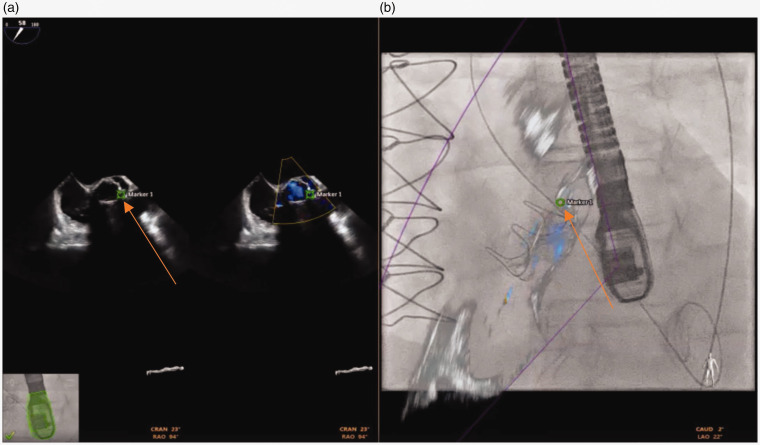

经导管技术越来越多地用于瓣旁泄漏闭合。我们报告使用“融合技术”(EchoNaviagator, Phillips, Tustin, CA),将实时二维和三维经食管超声心动图与透视成像相结合,以促进瓣旁泄漏闭合。这有助于确定瓣旁泄漏的确切位置、大小、深度和形状,以便正确定位封堵器装置,从而节省时间和精力。

Transcatheter technology has been increasingly used for paravalvular leak closure. We report the use of "Fusion Technology" (EchoNaviagator, Phillips, Tustin, CA) that combines real-time 2 and 3 dimensional trans-esophageal echocardiography with fluoroscopy imaging to facilitate paravalvular leak closure. This could help to identify the exact site, size, depth and shape of the paravalvular leak for proper positioning of the occluder device, which may result in saving time and effort.